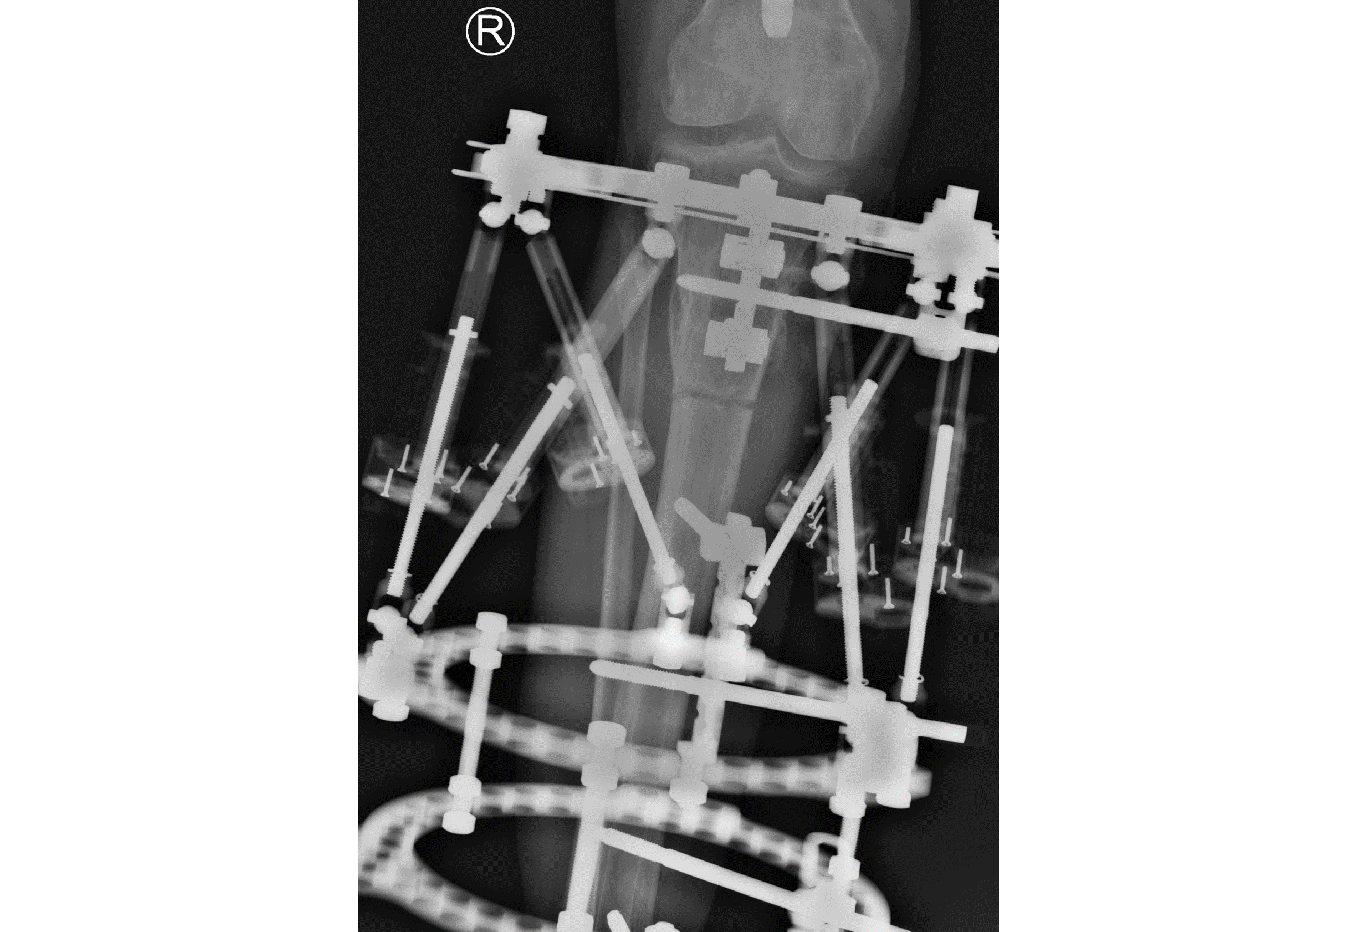

- 47-year-old woman s/p separate femur and tibia trauma

- Valgus knee with external rotation through femur

- Deformity analysis revealed that the angular deformity was coming from her proximal tibia.

The treatment plan was to remove the femoral intramedullary (IM) nail, to perform a derotational osteotomy of the femur with an internal saw, and then to refix the femur with a new antegrade IM nail.

The tibial deformity was planned to be managed with a MAXFRAME AUTOSTRUT™.